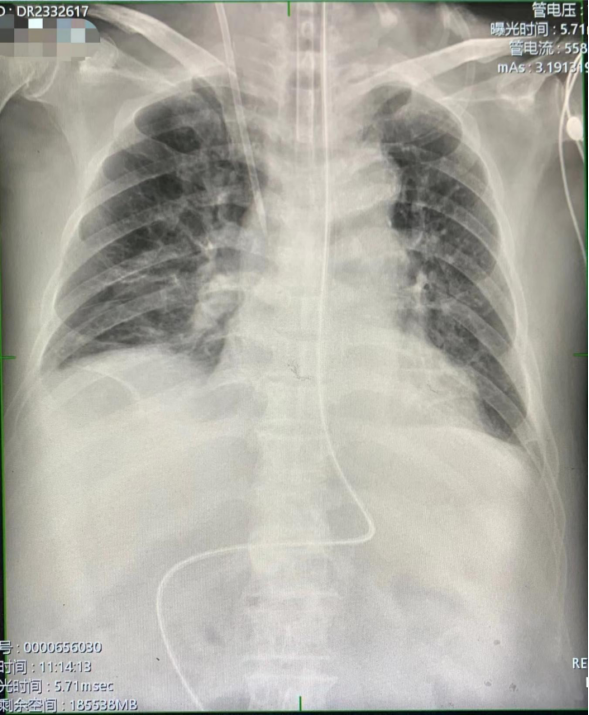

最后行腹平片检查后,结果显示空肠管尖端到达空肠,位置良好,确认置管成功。